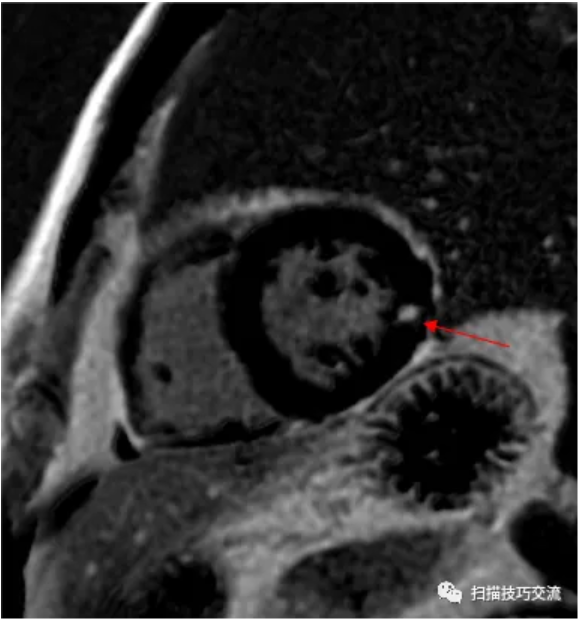

来看一例心脏LGE, 如果说,这个病例是心肌梗死

心肌中段:前壁和下壁的心内膜下的梗死(红箭),前间隔壁透壁性梗死(绿箭) 因为, 所有业内大牛都说,

最开始,心内膜下强化出现, 因为冠脉垂直插入心肌, 且在舒张期供血, 所以,心梗最先发起点都是心内膜下, 如果得不到及时救治 会蔓延到心肌全层